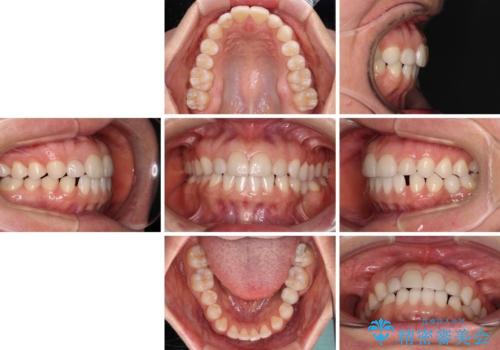

- 大きすぎる上顎前歯と、隙間の空いた下顎歯列を気にして来院された患者様です。

上顎前歯にはセラミッククラウンが装着されており、顔や他の歯と比較して幅の大きい状態でした。

下顎前歯は空隙歯列弓であったので、アンカースクリューとワイヤー装置を用いてスペースを閉じていくこととし、上顎前歯は矯正治療用の仮歯に置き換えた上で、仮歯の大きさを削って小さくしながら、上下前歯部の部分矯正を行うこととしました。

矯正治療後は、仮歯とした上顎前歯をオールセラミッククラウンにて補綴治療を行うこととしました。

日本と海外を拠点に仕事をされていらっしゃるため、数ヶ月治療があいてしまうことがあり、期間はかかりましたが、2年間で望み通りの前歯に仕上げることができました。